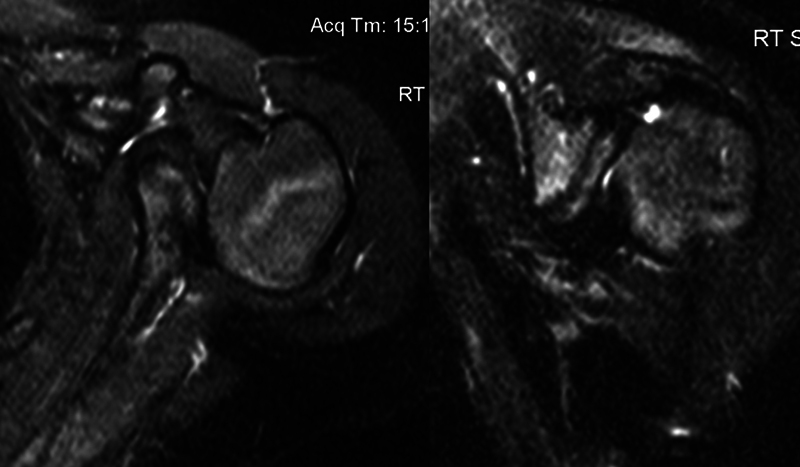

Abstract Image